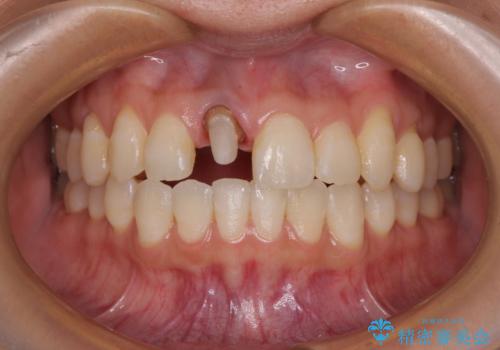

- 以前他院にて保険診療で治療した前歯のやり替え希望の患者様です。

被せものと土台の境目が段差になっています。

審美的にも清掃性の観点からも理想的とは言えない状態です。